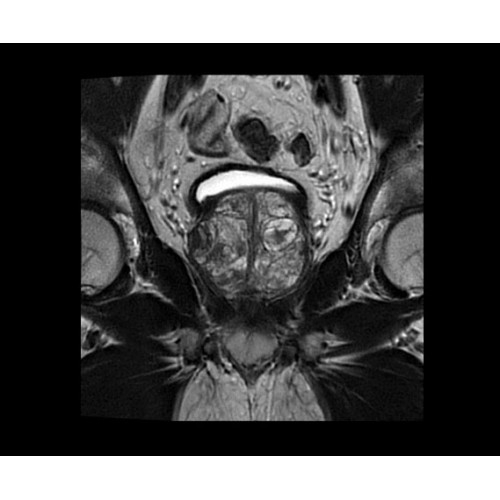

SIGNA PET/MR 3.0T — это гибридная система, в которой совмещаются две принципиально разные технологии — магнитно-резонансную томографию (МРТ) и позитронно-эмиссионную томографию (ПЭТ). Система отличающийся высокой чувствительностью и эффективностью и предназначена для диагностики в области онкологии, неврологии, кардио-васкулярных исследований, исследований воспалительных процессов.

Компания GE Healthcare представляет революционную, полностью интегрированную систему SIGNA PET/MR1, в которой сочетаются времяпролетная технология (TOF) и возможности напряженности магнитного поля 3.0 Тл. Мы поможем вам поднять исследования на более высокий уровень. SIGNA PET/MR позволяет достичь впечатляющей точности и скорости исследований, а благодаря новейшей технологии реконструкции Q.Clear2 качество изображений улучшается в два раза. Кроме того, в систему включен полный набор клинических приложений и гибких катушек для проведения любых видов исследования, открывая для вас возможности визуализации, о которых вы даже не догадывались.

В систему SIGNA PET/MR встроены запатентованные детекторы кремниевого фотоумножителя (SiPM) и сверхчувствительные кристаллические сцинтилляторы на основе лютеция толщиной 25 мм. Благодаря этому обеспечивается исключительная чувствительность и возможность использования времяпролетной диагностики (TOF).

Кроме того, в результате использования технологии TOF и инновационной технологии реконструкции Q.Clear вы сможете добиться прекрасного соотношения сигнал/шум. А благодаря технологии нулевого времени эхо (ZTE) визуализировать костную структуру без ионизирующего излучения. Все эти разработки для улучшения качества сканирования и точности анализа помогут вам использовать весь потенциал ПЭТ/МРТ.